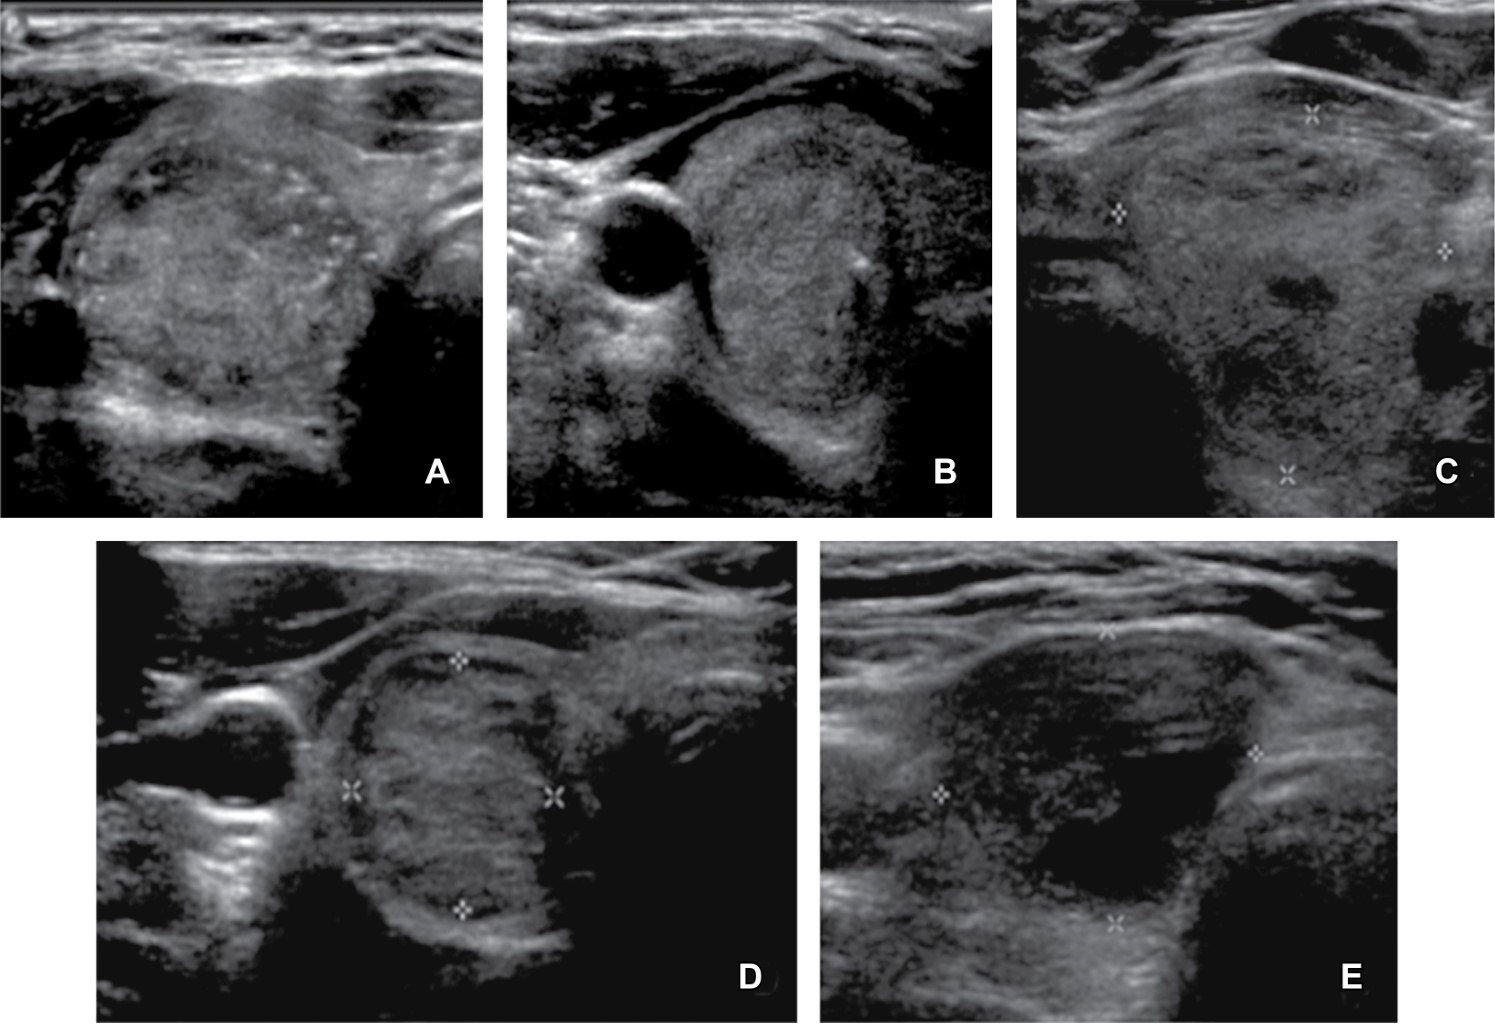

De 100% (29) de casos con resultado histopatológico de malignidad, 82.8% (24) presentaron datos ultrasonográficos que requirieron BAAF por cumplir con parámetros sugestivos de malignidad (Figura 1) y 17.2% (5) no cumplían datos para sugerir BAAF; entre estos cinco pacientes se engloban a los nódulos que por tamaño no cumplieron criterio para BAAF y, por TI-RADS-ACR, se hubiera sugerido seguimiento antes de cualquier procedimiento invasivo (Figura 2).

Entre los hallazgos por ultrasonido observamos que la mayor incidencia en los nódulos con resultado de malignidad fueron la composición sólida, la ecogenicidad que osciló entre hipoecoico y marcadamente hipoecoico, el margen lobulado o irregular y la presencia de macro y microcalcificaciones. Sin embargo, el dato con menor significancia fue la forma, la cual no tuvo ninguna diferenciación específica; se menciona esto porque es un dato al cual TI-RADS-ACR le otorga una alta calificación de tres puntos, llevando al nódulo más alto que ancho a una clasificación mayor. Es un dato que requerirá estudiarse de forma particular para mejorar los parámetros de clasificación.